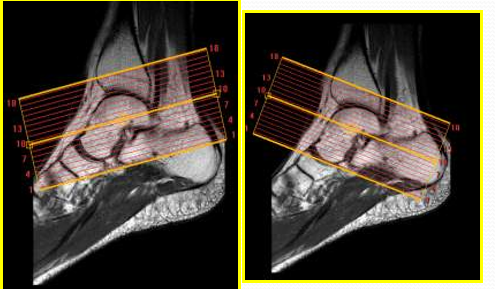

韧 带 显 示 技 术 要 点

T1WI及PDWI能清晰显示踝关节解剖,T2WI及脂肪抑制技术对显示病变有更大的帮助。横断面及冠状面能够显示大多数的韧带,应首先考虑行横断面和冠状面扫描,矢状面作为适当的补充

不同可疑韧带损伤的韧带选择最佳扫描层面:

①距腓前韧带:以20°斜断面效果最佳

②跟腓韧带:以-15°斜断面效果最佳